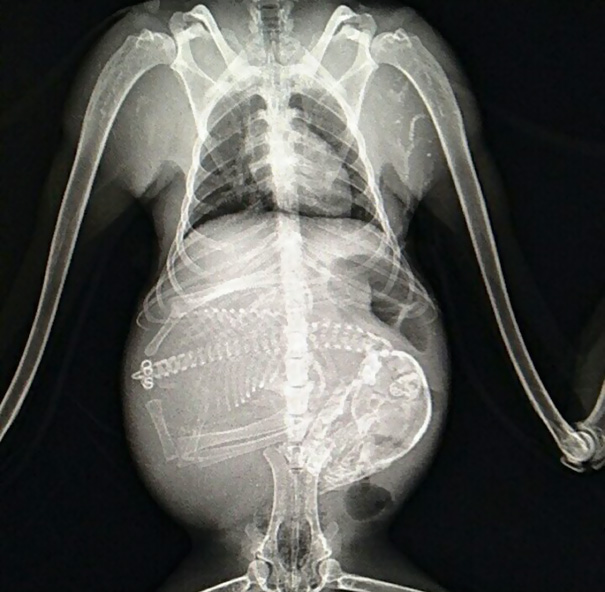

It's a common thing among humans to share X-ray pictures of babies still in the womb. However, even if you think you've seen it all, these X-ray pictures of baby animals still in their mommas' bellies are something that will make you say 'OMG'!

Load More Replies...An X-Ray Of A Pregnant Francois Langur Monkey